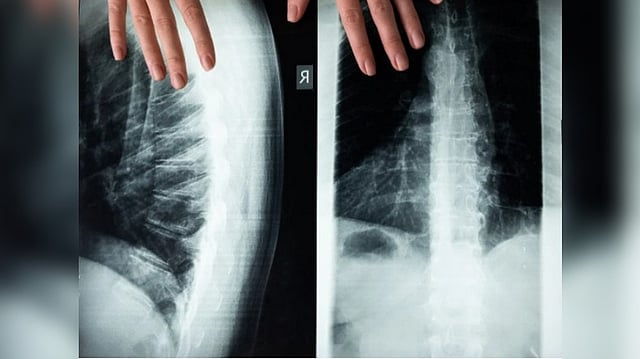

Research brings hope for the treatment of spinal cord injuries

Researchers used animal models to demonstrate that AZD1236 can promote significant nerve regeneration, with a dramatic 80 per cent preservation in nerve function following spinal cord compression injury.